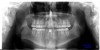

Figure 7 The panographic radiograph shows the roots of the cuspids encroaching upon the edentulous spaces. Additional orthodontic treatment will be required before implants can be placed to replace the missing teeth.

Figure 7